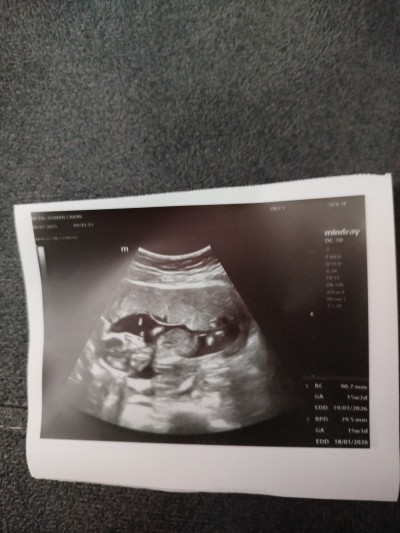

Kızlar 3 hafta önce gittim 12 haftalıkti Dr Cinsiyeti erkeğe benzettim dedi bugün gittim 15+3 haftalık cinsiyeti göstermedi bacakları kapalı dedi tahminleriniz nelerdir

Gebelik haftası 15+3

Bende erkeğe benzettim şuan Benimkide erkek doğum yapmak üzereyim benimde böyle duruyordu o haftalarda zaten erkek solda duruyor kız sağda seninki de sol tarafında duruyor

Bende erkeğe benzettim benim oğluşumda bu şekilde duruyo haftalarımız da yakın.